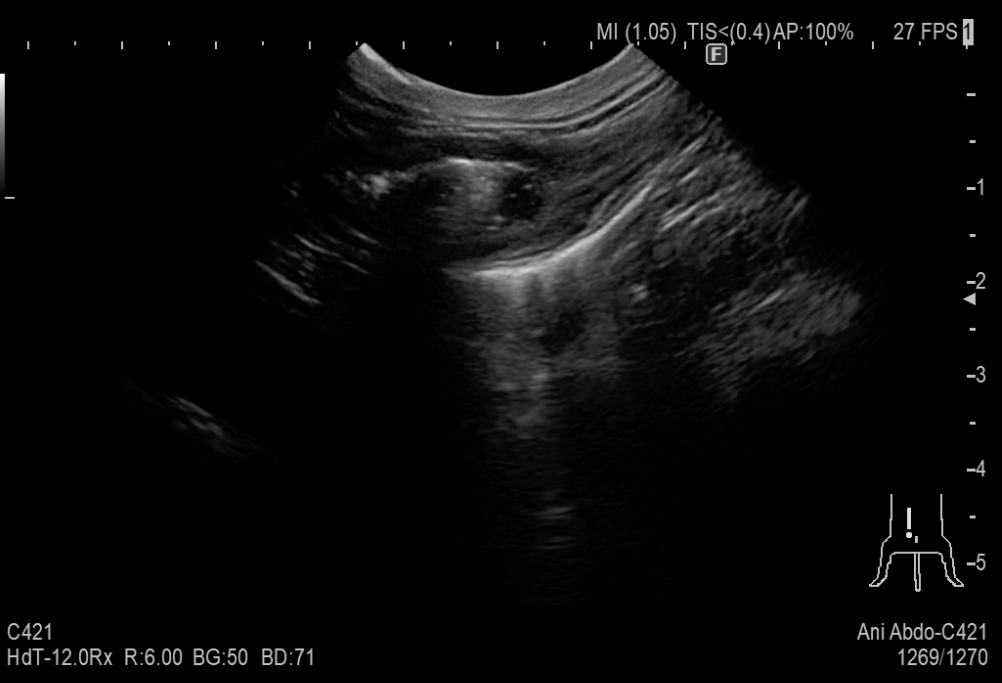

嘔吐を繰り返している8歳の猫が来院しました。

超音波検査にて消化管に腫瘍らしきできものが認められたため摘出を行いました。腹水が認められ、腹水の成分から腹腔内に炎症があることが分かりました。